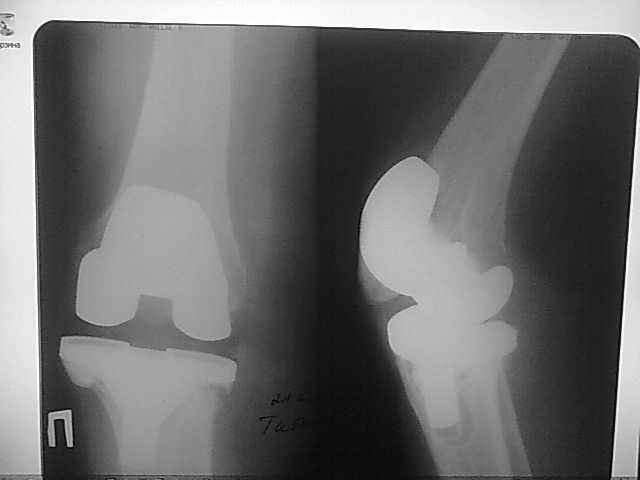

Уважаемые коллеги, прошу Вашего совета по тактике лечения. Женщина 1952 г.р., оперирована в 2006, в одной клинике установлен эндопротез правого коленного сустава, через год нестабильность обоих компонентов, доктор выполняет ревизию обычным протезом с задним стабилизатором. В октябре 2008 - нестабильность, свищ. В другом стационаре все удалено, спейсер с гентамицином, длинный курс антибиотиков. Коллатеральных связок нет. Собственная связка надколенника цела. До удаления протеза - выраженная смешанная контрактура. Сейчас свищей нет, анализы в порядке.

Планы: Стоит выбор 1) Обычный hinge с цементными ножками, вставками под тибиальным и бедренным компонентами с импакционной костной пластикой аллокостью с применением сеток для удержания трансплантата на tibia; 2) Онкологический hinge - с замещением проксимальной голени и сохранением бедра; 3 - артродез.

Мне очень хотелось узнать мнение коллег на предмет - если ставить простой hinge с костной пластикой - стоит ли использовать только костную крошку или необходим структурный костный аллотрансплантат? Есть ли у кого-то положительный опыт таких операций? Душа у меня не лежит использовать онкологическим протез для голени, т.к. пациентка слишком молода и сохранена собственная связка надколенника.